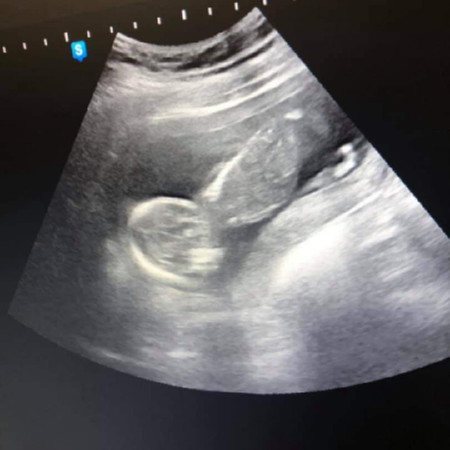

ท้องได้4เดือนแล้วค่ะ ไปอัลตร้าซาวด์มาเห็นลูกนอนตีลังกาตามรูปที่แนบมาค่ะ แบบนี้จะเป็นอันตรายมั้ยคะ

เหมือนลูกกลับหัวแล้วเหรอคะ แล้วคุณหมอว่าไงบ้างคะ